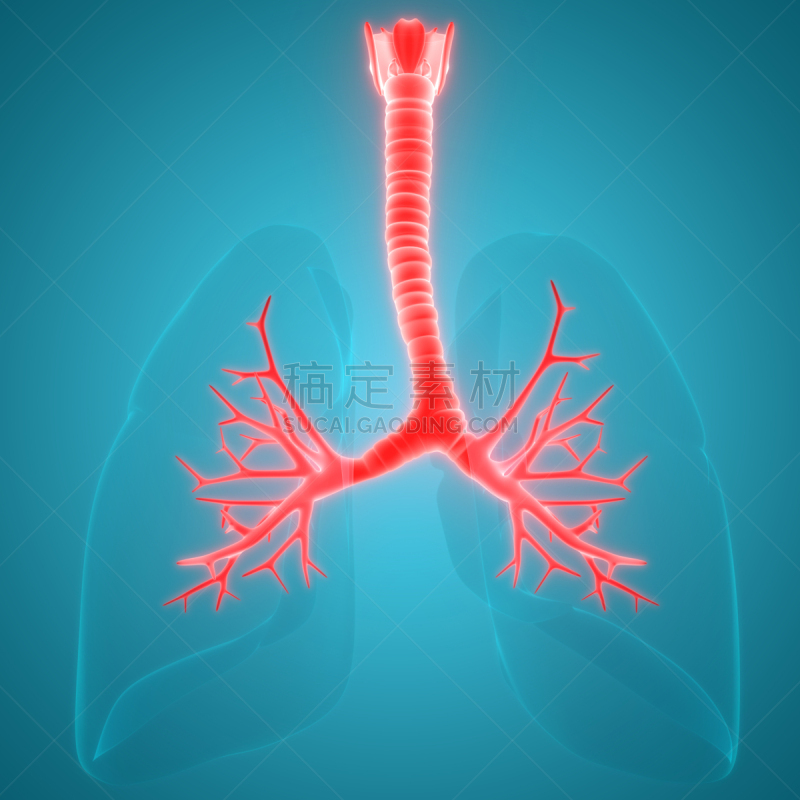

人体呼吸系统肺解剖学详情

JPG

人体呼吸系统肺解剖学详情

JPG

人体呼吸系统肺解剖学详情

JPG